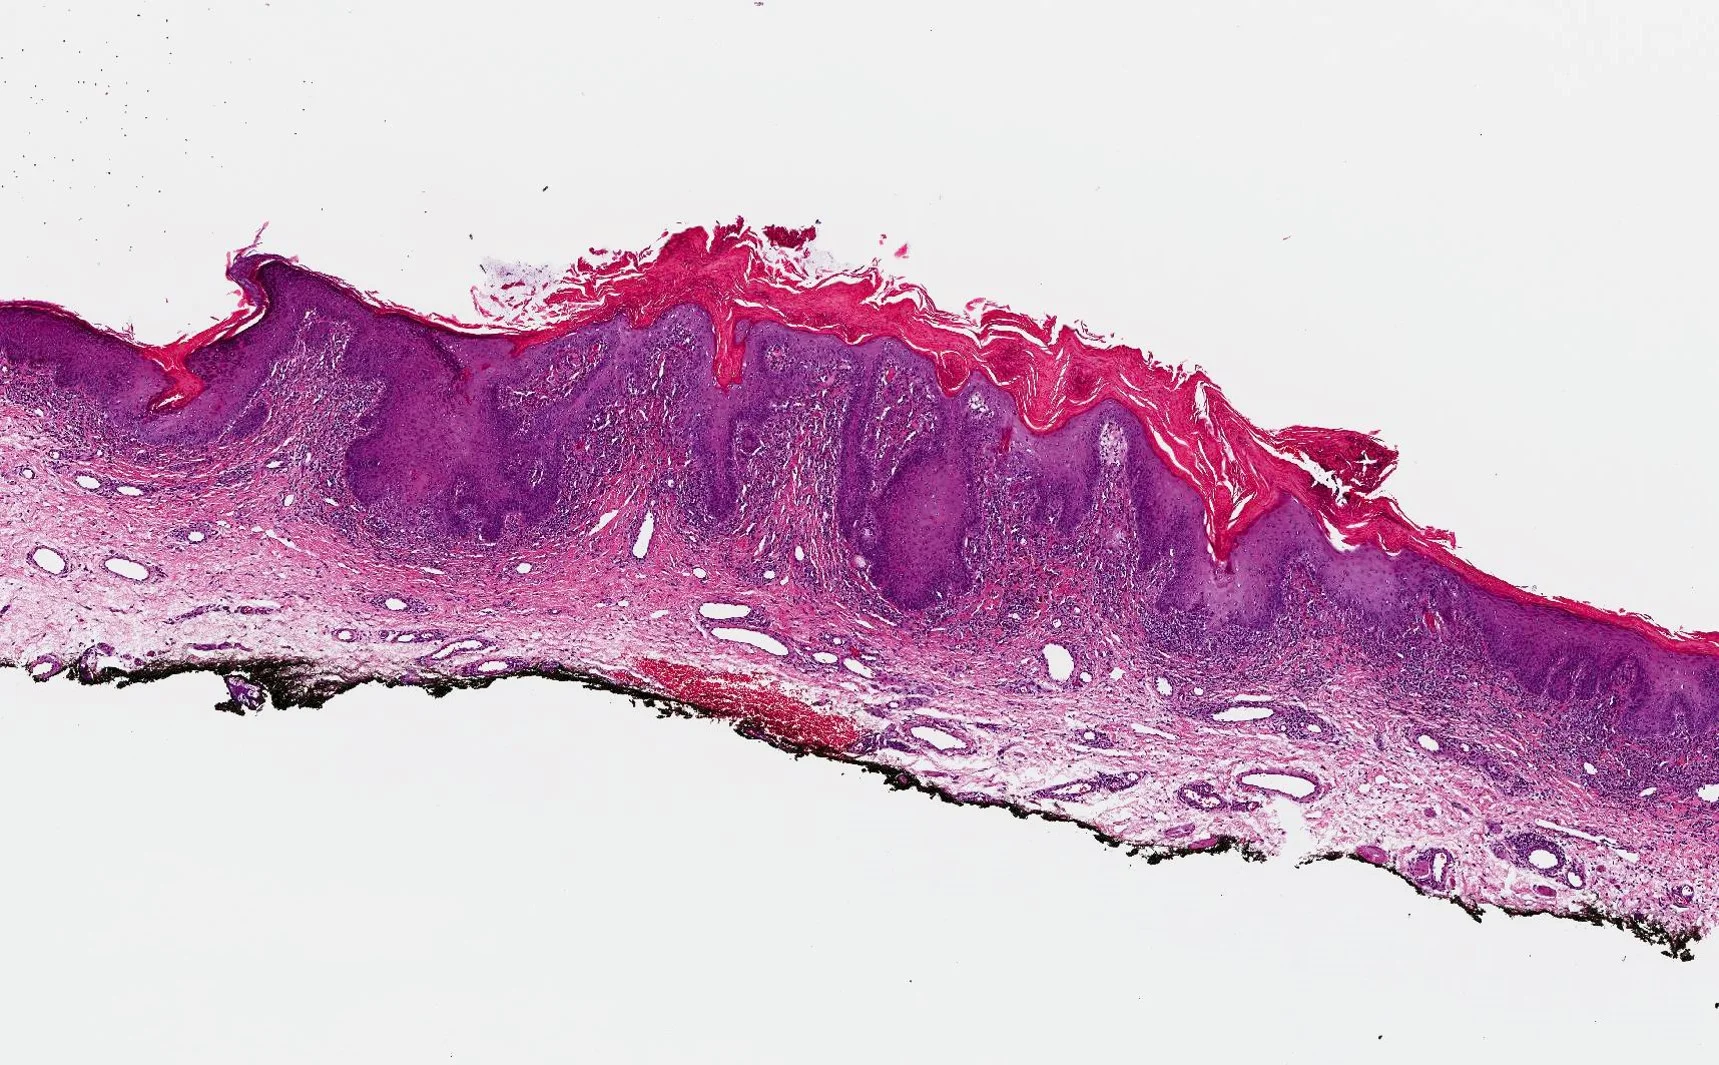

Case 18: Pigmented Fungiform Papillae of the Tongue: An Incidental Finding in a Patient with Mycosis Fungoides

History: A 28-year-old Hispanic male with history of Stage IA mycosis fungoides presented with “new dark spots on the tongue.” He denied pain or pruritus. He also denied ever having taken minocycline or any prescribed medications. He did endorse daily intake of omega 3 and a multivitamin. Past dermatologic diagnoses included a halo nevus, generalized xerosis treated with Cetaphil, and idiopathic guttate hypomelanosis on the back. At the current visit, he denied systemic symptoms. His mycosis fungoides had been clinically stable for the past five years with home, narrowband UVB light phototherapy twice a month.

Physical Examination: Physical examination of the oral cavity was significant for multiple dark-brown structures on the distal tongue. Dermoscopic evaluation showed several fungiform papillae with pigmented borders in a rose petal pattern. No other unusual hyperpigmented lesions were seen on the body.

Histopathology: A shave biopsy of tongue showed papillae with melanophages in the lamina propria.

Diagnosis: Pigmented fungiform papillae of the tongue

Points of Emphasis: Normal fungiform papillae of the tongue are pink “mushroom-shaped” projections predominantly located on the lingual margin but also irregularly distributed on the dorsal surface of the tongue. Pigmented fungiform papillae (PFP) are considered a normal variant with increased pigmentation. The finding is more prevalent in individuals with darker skin but the pathogenesis remains unclear. Other pigmented lesions of the oral mucosa include Peutz-Jeghers syndrome, hemochromatosis, Addison’s disease, black hairy tongue, melanocytic nevi and melanoma. Multiple medications and exogenous substances such as amalgam tattoo, anti-malarials and antibiotics can also cause mucosal pigmentation. While some of these entities can be differentiated from PFP on clinical grounds alone, dermoscopic patterns can be extremely helpful in distinguishing this entity from other melanocytic conditions. Benign lesions can show one or several patterns with a regular distribution, while melanomas tend to have several patterns which are irregularly distributed. A rose petal pattern is more consistent with PFP. In our case, dermoscopy was a helpful tool in distinguishing possible melanocytic oral processes from this uncommon normal variant of lingual papillae. Its use should be encouraged as part of a detailed physical examination of the oral mucosa in similar situations, in order to avoid incorrect diagnoses and unnecessary testing. Microscopic studies could be performed in cases of remaining diagnostic uncertainty.